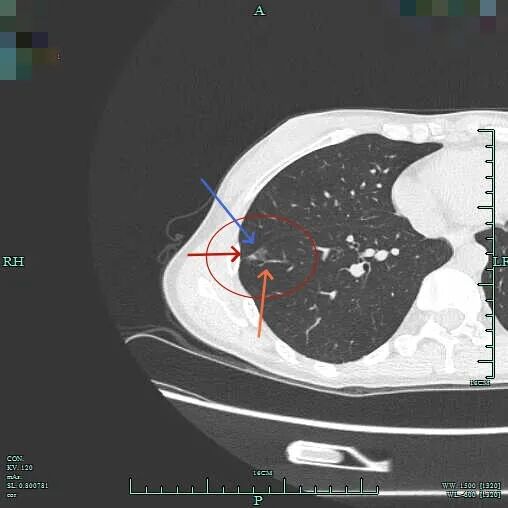

上叶病灶B也是磨玻璃密度的,轮廓与边界清。

上叶病灶D邻近病灶B,但太微小,也很淡。

下叶病灶C也是磨玻璃密度,但位置较深,在前基底段与内基底段交界附近,考虑不典型增生或原位癌可能性大,尤其是前者。